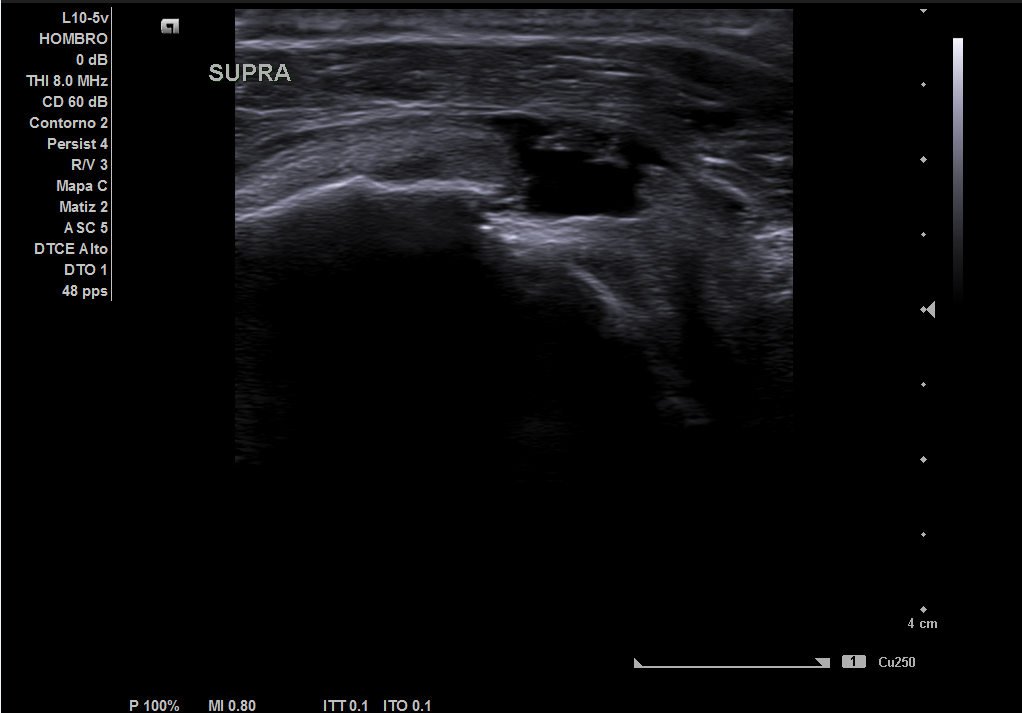

Descripción de los hallazgos ecográficos y las imágenes más relevantes para la resolución del caso

En la ecografía realizada observamos una rotura completa del tendón supraespino, rotura parcial del subescapular y severo derrame peritendón del bíceps junto con derrame articular glenohumeral.